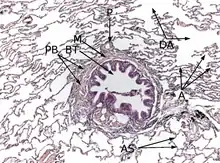

Coloration à l'hématoxyline et à l'éosine (HE).

L'interstitium (tissu de soutien) du poumon est constitué de septums interalvéolaires, situés entre les parois des alvéoles pulmonaires. Ces dernières, siège de l'échange gazeux entre sang et air, forment le tissu proprement fonctionnel du poumon (parenchyme). L'interstitium et le parenchyme coopèrent étroitement au fonctionnement du poumon, et constituent une unité fonctionnelle. L'interstitium constitue l'armature de base du poumon et soutient l'architecture des alvéoles, c'est-à-dire de la barrière sang-air pendant le cycle de la respiration. Cet interstitium est constitué de cellules, avant tout spécialisées dans le soutien (fibroblastes), de protéines structurales qu'elles produisent, et en substances telles que le collagène, les fibres élastiques, les protéoglycanes ainsi que d'autres glycoprotéines.